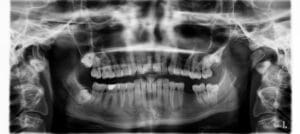

Tip 2. Wees je bewust van röntgenstraling

Röntgenstraling is voor niemand gezond. Volg je gevoel als je tandarts röntgenfoto’s wil maken. Je kunt bijvoorbeeld aan je tandarts vragen of die enkel röntgenfoto’s wil maken als die dat noodzakelijk acht.

Ik had eerst een tandarts die nooit röntgenfoto’s maakte. Op een gegeven moment kreeg ik een tandarts die vaak röntgenfoto’s wilde maken. Dat voelde voor mij niet fijn. Ik heb toen afgesproken dat er enkel röntgenfoto’s worden gemaakt als dit noodzakelijk is, bijvoorbeeld als de tandarts een gaatje vermoedt.